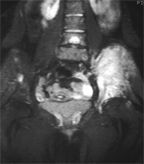

MRI diagnoses Ewing's sarcoma of the right hip